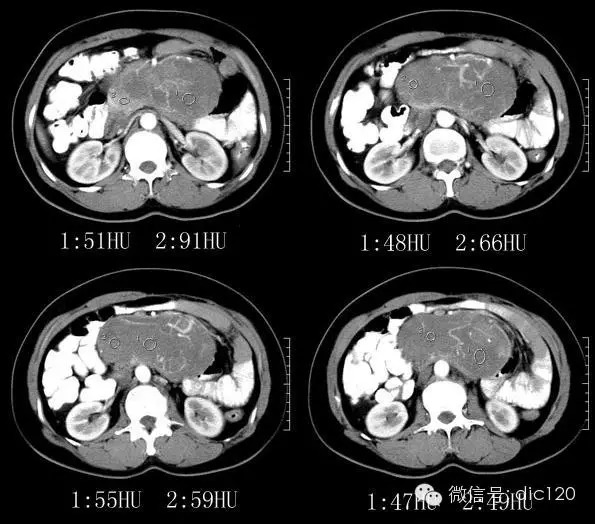

【影像图片】

平扫:腹膜后区域可见形态略不规则的类椭圆形肿块影,密度比较均匀;边缘大部分清晰,与主动脉和部分肠壁的边缘模糊,且脂肪间隙消失;周边脂肪的密度比较均匀;肠系膜上动脉,肠系膜上静脉,肠系膜及肠管向前方和侧方受压移位明显;腹腔内未见明显的肿大淋巴结。增强:动脉期肿块强化并非明显,但可见增多、增粗、迂曲的供血血管影;静脉期肿块强化的略明显,且略有不均匀,可见形态不规则的低密度轻微强化或者不强化的区域。

3.增强渐进明显强化,内部示粗大较规则血管影;定位:后腹膜;定性:低度恶性间叶组织来源肿瘤>神经源性肿瘤。